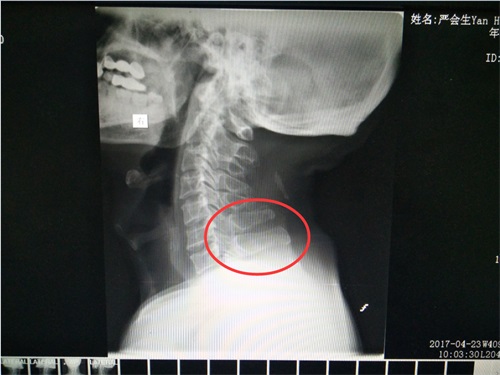

▲C4/C5、C5/C6、C6/C7部位椎间盘突出图